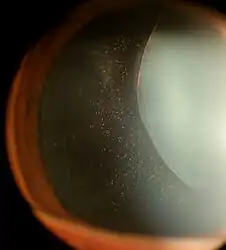

The zonules of Zinn are difficult to visualize using a slit lamp, but may be seen with exceptional dilation of the pupil, or if a coloboma of the iris or a subluxation of the lens is present.[8] The number of zonules present in a person appears to decrease with age.[5] The zonules insert around the outer margin of the lens (equator), both anteriorly and posteriorly.[9]